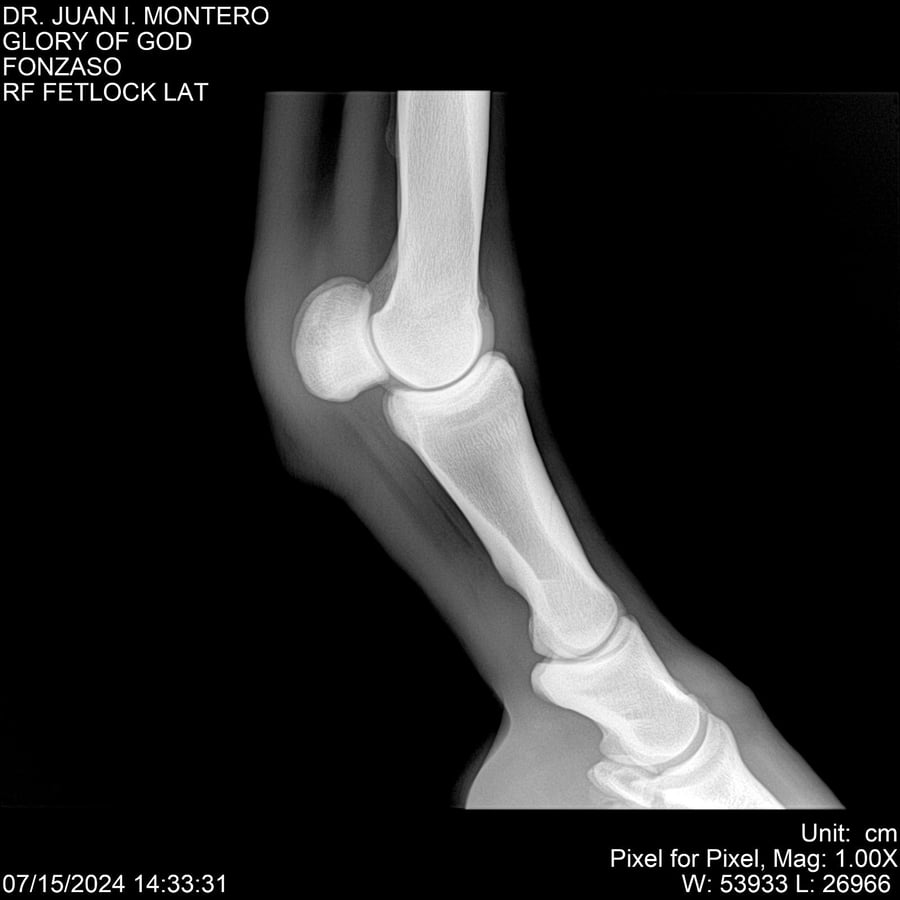

LOTE 10, GLORY OF GOD 🔥 🔥 🔥 Lote Anterior Volver al remate Lote Siguiente Ficha Contacto Montevideo - Ficha del Lote Identificador: #281389 Categoría: Yeguarizos Montevideo - 115 Visualizaciones ClicData Contacto Empresa: Abelenda N. R., Walter Hugo Nombre*: Teléfono* : E-mail* : Mensaje Enviar Registrese gratis Este contenido Exclusivo está disponible sólo para usuarios registrados Ingresar